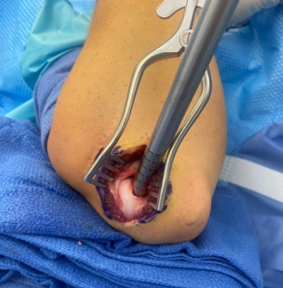

Arthroscopic examination of an OCD lesion

- Elbow arthroscopy is used for fragment excision, loose body removal and debridement for small unstable fragments

- Large unstable lesions in skeletally immature elbows are indicated for osteochondral autograft transplantation where cartilage can be harvested from a donor site (typically knee) and transferred to elbow lesion to restore normal healthy cartilage